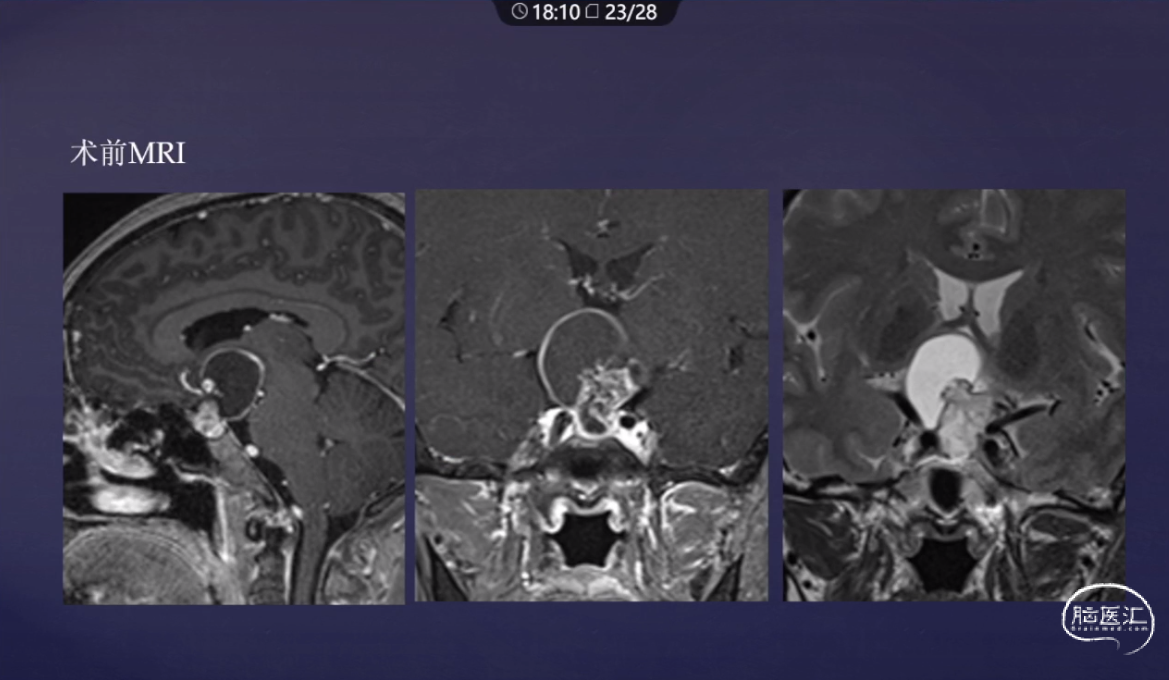

洪涛教授:经鼻内镜颅咽管瘤切除术

本文从内镜下颅咽管瘤分型,下丘脑损伤分级,不同分型颅咽管瘤术中要点,结合病例多角度为大家分享经鼻内镜颅咽管瘤切除术。